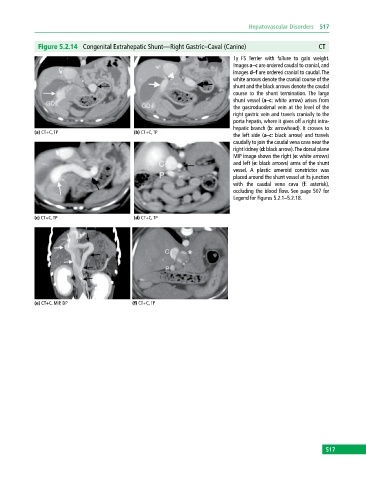

Figure 5.2.14 Congenital Extrahepatic Shunt—Right Gastric–Caval (Canine) CT

1y FS Terrier with failure to gain weight.

Images a–c are ordered caudal to cranial, and

images d–f are ordered cranial to caudal. The

white arrows denote the cranial course of the

shunt and the black arrows denote the caudal

course to the shunt termination. The large

shunt vessel (a–c: white arrow) arises from

the gastroduodenal vein at the level of the

right gastric vein and travels cranially to the

porta hepatis, where it gives off a right intra-

hepatic branch (b: arrowhead). It crosses to

(a) CT+C, TP (b) CT+C, TP

the left side (a–c: black arrow) and travels

caudally to join the caudal vena cava near the

right kidney (d: black arrow). The dorsal plane

MIP image shows the right (e: white arrows)

and left (e: black arrows) arms of the shunt

vessel. A plastic ameroid constrictor was

placed around the shunt vessel at its junction

with the caudal vena cava (f: asterisk),

occluding the blood flow. See page 507 for

Legend for Figures 5.2.1–5.2.18.